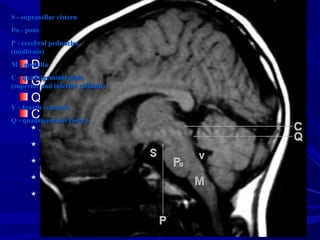

S - suprasellar cisternS - suprasellar cistern

Po - ponsPo - pons

P - cerebral pedunclesP - cerebral peduncles

(midbrain)(midbrain)

M - medullaM - medulla

C - quadrigeminal plateC - quadrigeminal plate

(superior and inferior colliculi)(superior and inferior colliculi)

V - fourth ventricleV - fourth ventricle

Q - quadrigeminal cisternQ - quadrigeminal cistern